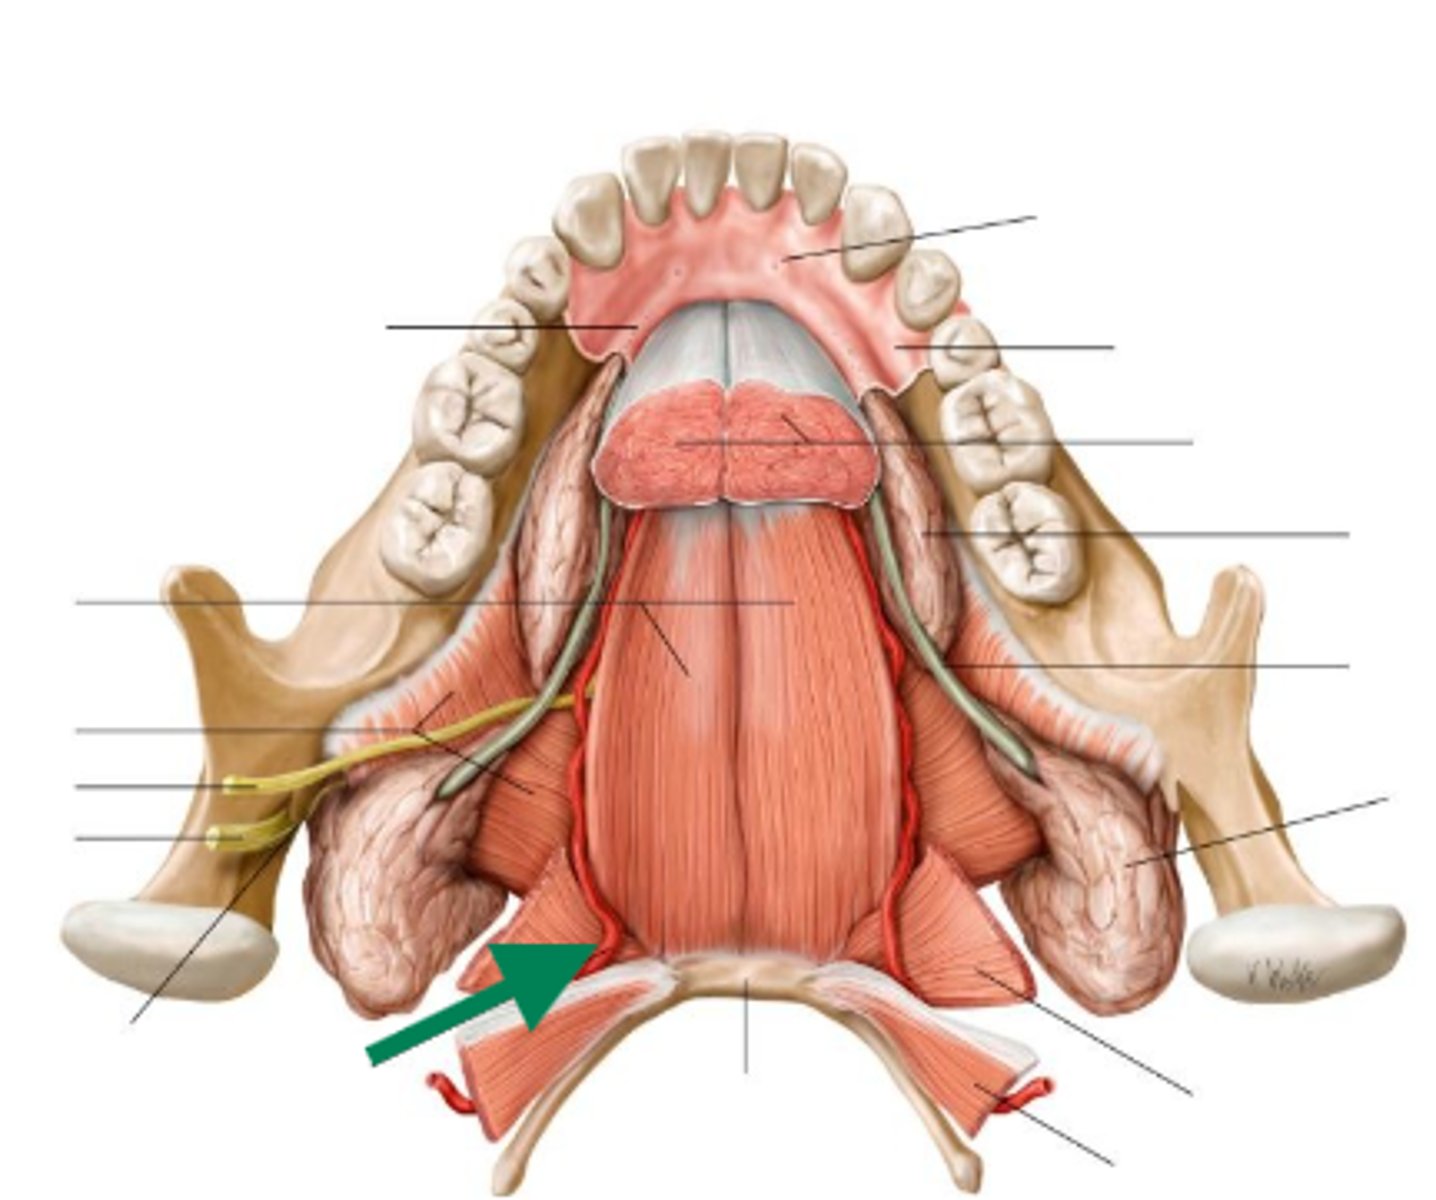

genioglossus

geniohyoid

mylohyoid

lingual artery

lingual nerve